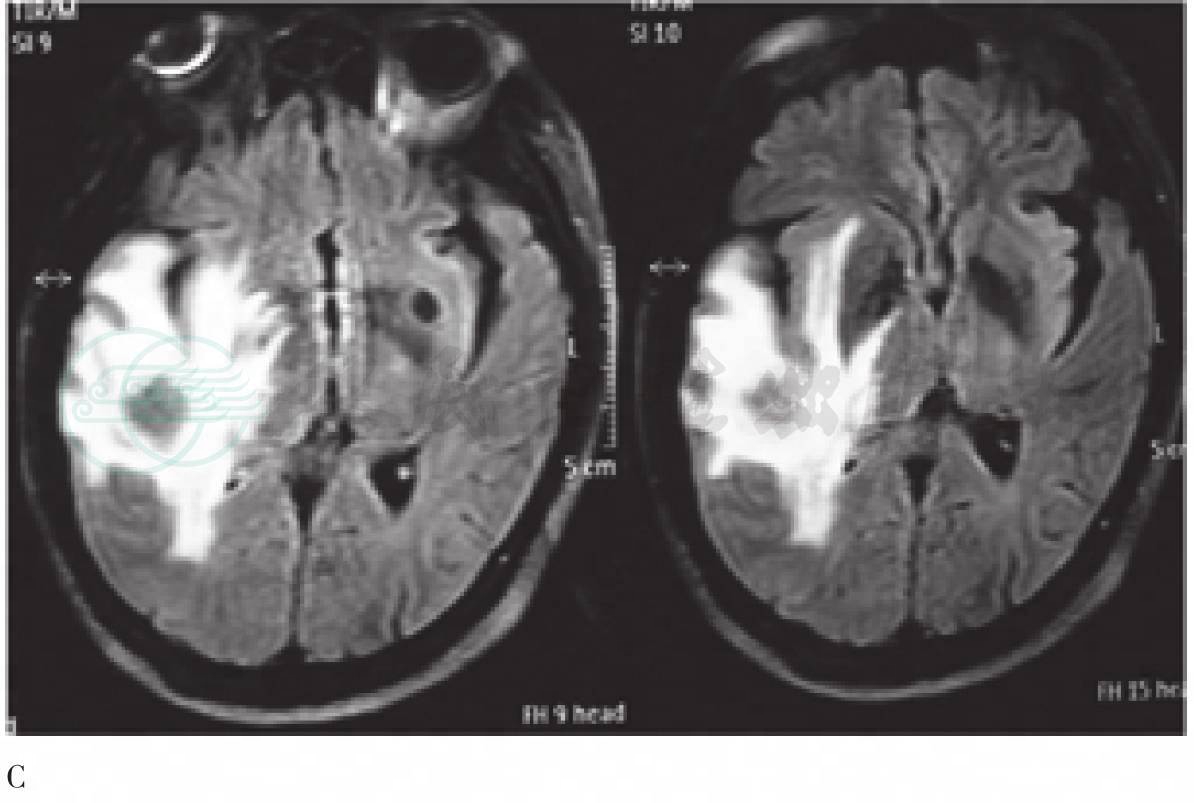

图4 右侧颞叶病变第二次MR图像

A. T1WI图像示病灶边界清晰,内部信号不均匀;B. T2WI图像示病变呈多层“环靶”样信号;C. FLAIR图像示周围水肿明显;D. 增强MR扫描示病灶环形强化

(2)第二次(图4):病灶明显增大,T1、T2WI呈等及混杂信号,T2WI呈多层环状,边界清晰,可见水肿,增强后环形强化。